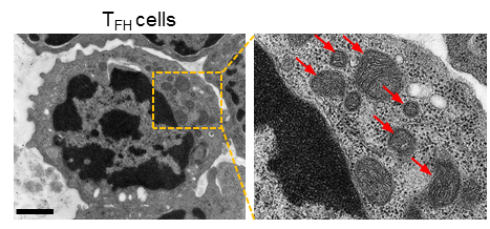

图2 透射电镜下看到TFH细胞内皱缩和损伤的线粒体,显出铁死亡特征 (图片来源于Nature Immunology)